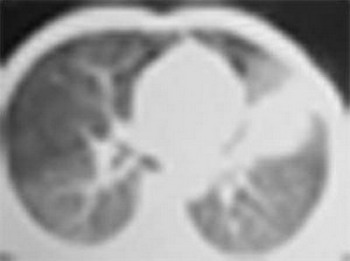

1).实变周围有渗出性病变(见肺窗片);

4).实变灶内密度失均,有少量短管状气影,可能为合并之支扩.

左肺内不规则影近似长条状,边缘较模糊,考虑左胸叶间积液伴周围渗出;

除大家上述征像外,左侧胸廓轻度内陷,纵隔影轻度左移,说明可能有肺不张,因而应首先考虑肿瘤的诊断。